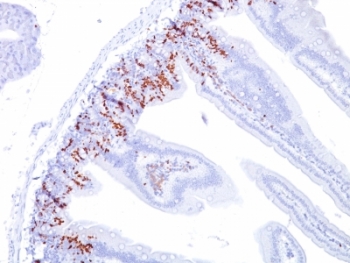

IHC: Formalin-fixed, paraffin-embedded mouse small intestine stained with BrdU antibody (BU20a).

It reacts with Bromodeoxyuridine (BrdU) in single stranded DNA (produced by partial denaturation of double stranded DNA), BrdU coupled to a protein carrier, as well as free BrdU. BrdU is a thymidine analog, incorporated into cell nuclei during DNA synthesis prior to mitosis. Antibody to BrdU is helpful in detecting S-phase cells, providing useful information on the aggressiveness of tumors.